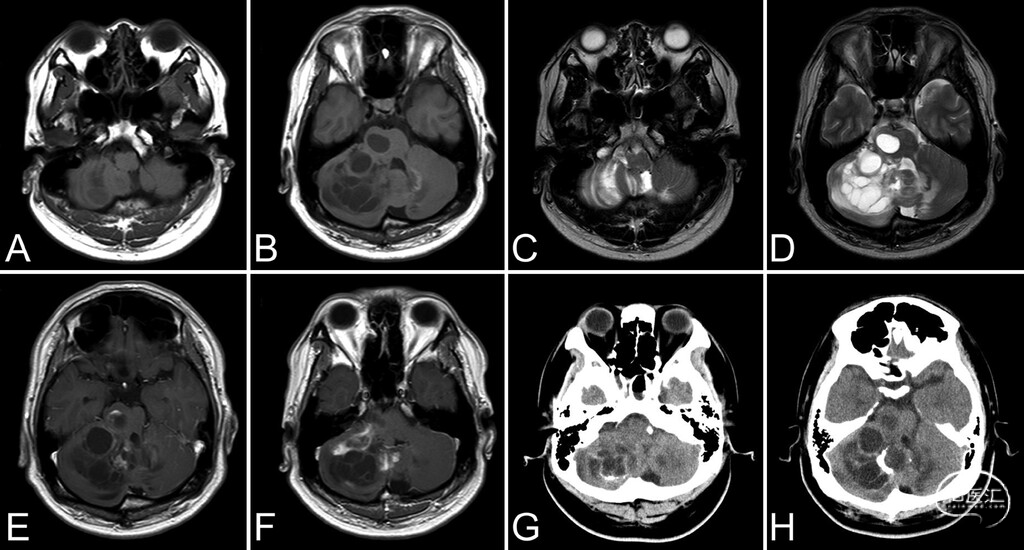

● 患者为20岁左右男性,因溺水被送往医院。头颅CT偶然发现一多房囊性伴钙化病灶,范围自右侧小脑半球延伸至脑桥。第四脑室虽受压,但未见脑积水。MRI显示病灶为多房囊性肿块,累及右侧小脑半球、小脑蚓及脑桥(图1)。T2加权MRI示小脑半球呈条纹状表现,伴轻度病灶周围水肿;钆增强T1加权MRI示病灶部分强化。

图1:术前影像。A、B:T1加权MRI示右侧小脑半球病灶呈低至等信号,可见线状条纹及多发囊性成分。C、D:T2加权MRI示多房囊性病灶,小脑皮质内可见平行高信号条纹。E、F:增强T1加权MRI示病灶内散在强化。G、H:CT示囊壁周围钙化。